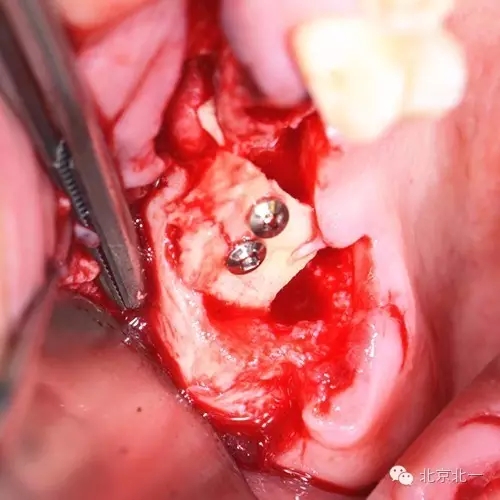

圖四:取骨區(qū),下頜智齒位置,取骨工具用超聲骨刀。

圖五:手術(shù)區(qū)可見拔牙窩

圖七:骨塊堅(jiān)強(qiáng)內(nèi)固定